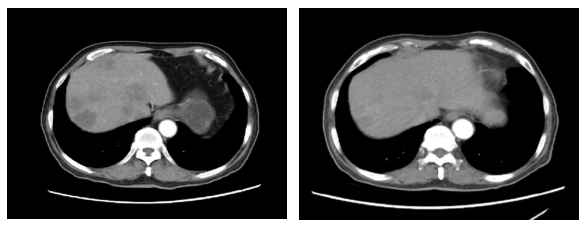

2020.4.12腹部CT:肝脏多发乏血供结节,较前明显减少并缩小(图4)。

图4. 腹部CT(左:2020.1.5,右:2020.4.12)